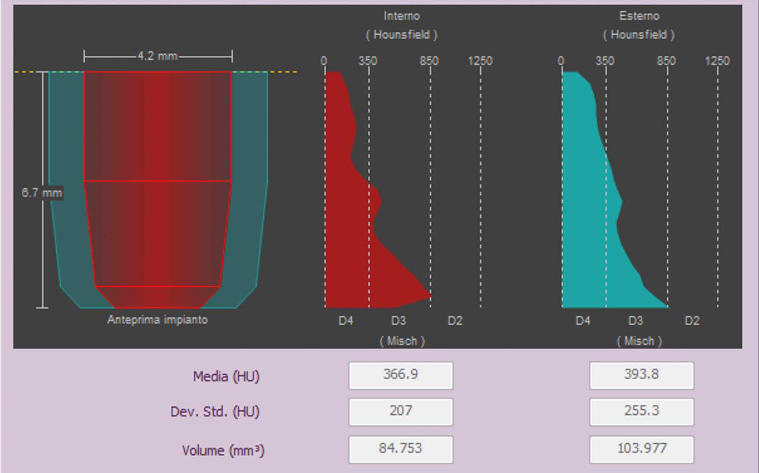

- Évaluation de la qualité de l’os

Analyses volumétriques

La fonction du logiciel de calcul du volume de soulèvement du sinus maxillaire permet de déterminer l’intervention à l’avance et d’opérer en toute sécurité. Il est en outre possible de tracer des lignes directement sur le modèle virtuel du patient en évaluant les rapports morphologiques sur le rendu 3D.

Évaluation des implants zygomatiques

Les volumes avec FOV 13 x 8 cm, ou 13 x 10 cm, représentent l’outil idéal pour la planification des implants zygomatiques. En effet, le diamètre de 13 cm est le seul qui permet d’inclure tout le zygoma dans le balayage, sans coupes.